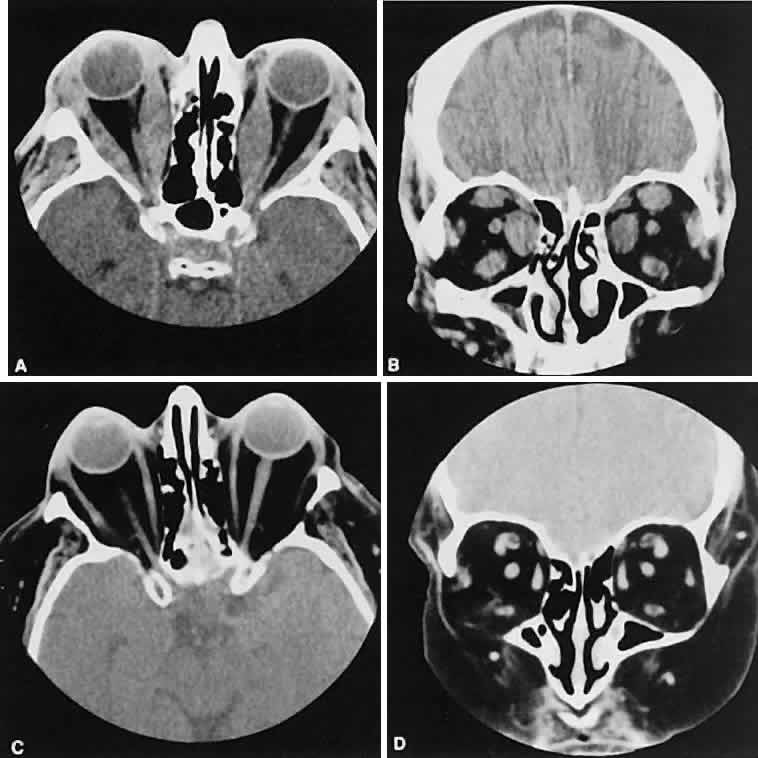

Malignant lesions of the lacrimal gland, conversely, often appear invasive, with bone destruction evident on the CT scan (Fig. 17). Intralesional calcium may be present.63,64 The use of contrast material facilitates detection of lesions that extend beyond the confines of the orbit.

Fig. 17. Adenocarcinoma of the lacrimal gland. A. Unenhanced axial view shows the speckled calcification of a lacrimal gland tumor. B. Contrast-enhanced view at about the same level shows intense enhancement and vascularity. In axial views at a higher level, an unenhanced scan (C) is unremarkable, although a contrast-enhanced view (D) at the same level highlights intracranial extension (arrows). E. Reconstructed coronal view has bone destruction with extension into the intracranial and temporalis fossae.